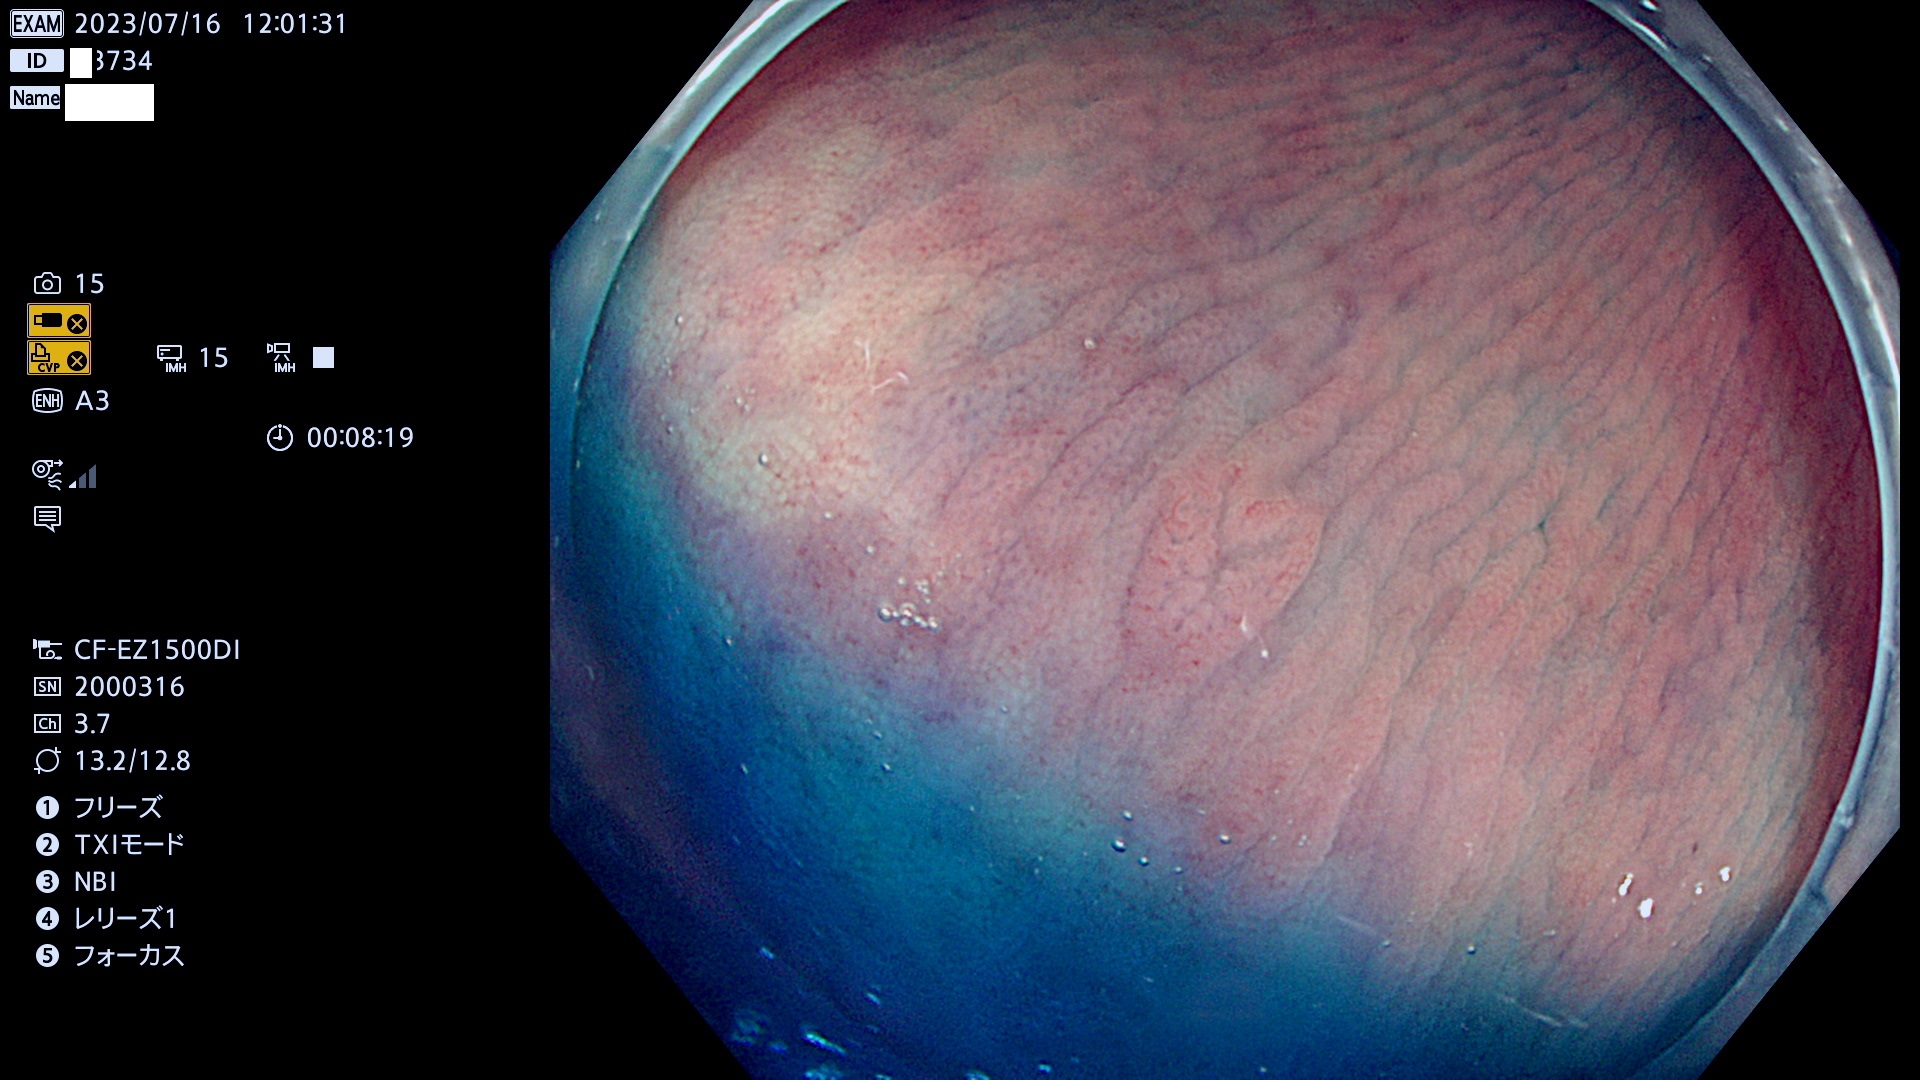

大腸Ub、Uc型・腺腫とは?

「表面型腺腫(Flat Adenoma)の中で、完全に平坦な物をUb、陥凹している物をUcと呼びます。平坦隆起型(Ua)よりも、発見が難しく危険な病変です。このタイプの発見率は「腺腫発見率」よりも、遥かに重要な意義があります。

毎週の検査(木・金・土・日)に発見されたUb、Uc型・腺腫を、その週の日曜の夜にUPし1週間、提示します。

抽出の対象期間 2023年7月13日(木)〜7月16(日)の4日間(48件の検査)8件